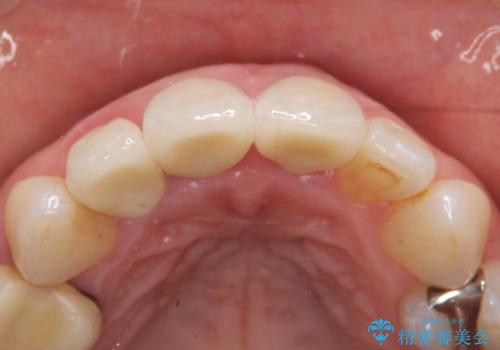

前歯の補綴ではオールセラミッククラウンを希望される患者様が多いですが、オールセラミッククラウンの中でも、エコノミー、スタンダード、スペシャル、エクセレントとランクがあります。

その中でも特に審美性が高いのがスペシャル、エクセレントです。スペシャル、エクセレントは口腔内写真をもとに熟練の技工士が、患者様の口腔内に合わせたオーダーメイドのクラウンを製作致します。

- オールセラミッククラウン(スペシャル)…¥130,000×3、仮歯…¥10,000×3、ファイバーコア…¥20,000×3費用は治療当時の料金となります